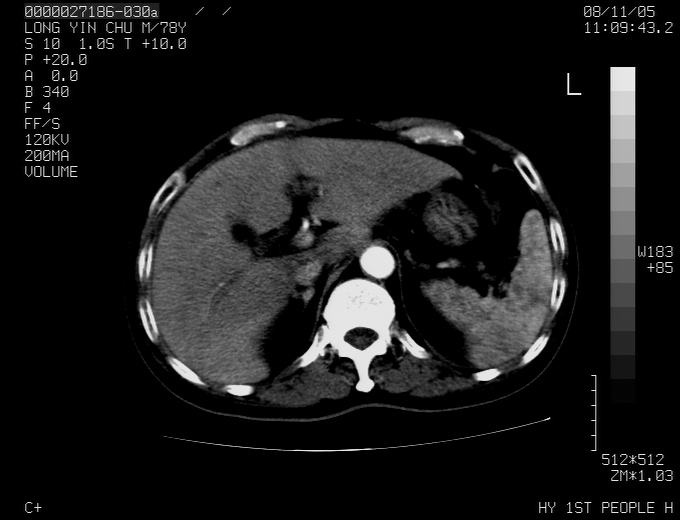

腹胀,腹痛就诊,男性,78岁,外院b超未见异常。

肝ca,脾肾转移

支持脾肾转移瘤,双侧胸腔积液。

考虑弥漫性肝癌并脾及双肾转移.双侧胸水.

图片质量欠佳:多考虑:左侧肾癌。脾脏转移!胸膜转移!

肝脾肾转移瘤可能性大,左肾不除外梗塞,双侧胸水

考虑肝癌并双肾及脾脏转移;双侧胸腔积液。